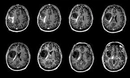

Bu belirtiler malign tümörlerin varlığını gösterebileceği gibi, başka sağlık sorunlarının belirtisi de olabilir. Bu nedenle, belirtilerin ortaya çıkması durumunda bir sağlık uzmanına başvurulması önemlidir. Malign Tümörlerin Tanı YöntemleriMalign tümörlerin tanısı, çeşitli yöntemler kullanılarak konulmaktadır. Bu yöntemler arasında:

Bu tanı yöntemleri, malign tümörlerin varlığını belirlemek ve tümörün türünü, evresini değerlendirmek amacıyla kullanılmaktadır. Erken tanı, tedavi sürecinde büyük bir öneme sahiptir. Malign Tümörlerin Tedavi SeçenekleriMalign tümörlerin tedavisi, tümörün türüne, evresine ve hastanın genel sağlık durumuna bağlı olarak değişiklik göstermektedir. Başlıca tedavi yöntemleri şunlardır: